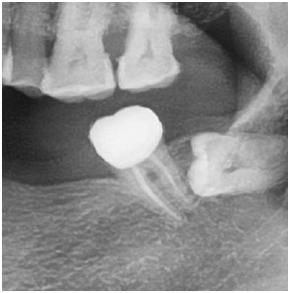

重点来了,来看看做得好的根管长什么样:

片子上可以很清晰地看出根管里面均匀地充满了不透光的材料(片子上白色的),把中空的根管恰好填满,看着就非常舒服~